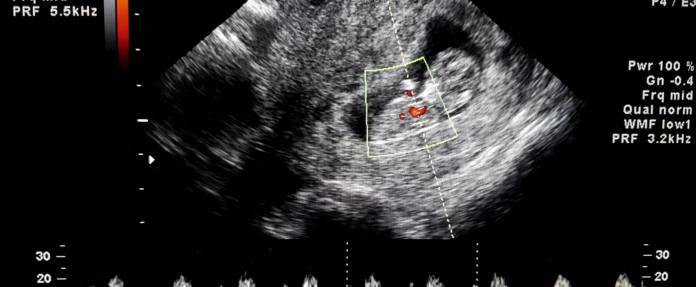

Solche angeborenen Herzfehler können bei einer gewissen Ausdehnung bereits im Mutterleib mittels Ultraschall festgestellt werden. Auch das Foramen ovale als natürliches Loch im Herz kann auf den Ultraschallbildern erkannt werden.

Etwa 8 bis 10 von 1.000 Neugeborenen kommen mit einem Herzfehler zur Welt. Ob bei einem Säugling ein angeborener Herzfehler zu erwarten ist, kann in vielen Fällen nicht erst nach, sondern bereits vor der Geburt festgestellt werden. Ultraschall-Untersuchungen können Aufschluss darüber geben, ob sich das Herz des Fötus normal entwickelt. Bereits ab der 14. Schwangerschaftswoche kann versucht werden, einer Fehlentwicklung auf die Spur zu kommen. Verlässliche Aussagen sind allerdings erst etwa ab der 20. Schwangerschaftswoche möglich. Zu dieser Zeit findet als Screening-Untersuchung ein Ultraschall statt, bei dem unter anderem nach Anzeichen für angeborene Herzfehler gesucht wird. Vorgeburtliche Ultraschall-Untersuchungen fördern vor allem besonders schwere Herzfehler zutage. Sie bieten sowohl den Eltern als auch den behandelnden Ärzten die Möglichkeit, sich auf mögliche Komplikationen oder Eingriffe in der Zeit unmittelbar nach der Geburt vorzubereiten. Einige Leiden können sogar bereits vor der Geburt behandelt werden.

Eine Fehlentwicklung am Herz kann ab der 20. Schwangerschaftswoche im Rahmen einer speziellen Ultraschalluntersuchung, dem sogenannten Vierkammerblick, festgestellt werden. Bei Auffälligkeiten ist eine weitergehende Ultraschalluntersuchung (fetale Echokardiographie) erforderlich.